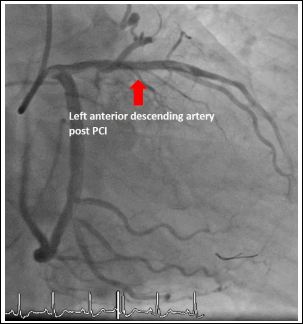

Our second case was a 67-year-old male with no prior cardiac history who presented with an acute anterior STEMI. Emergency coronary angiography revealed a single coronary artery with a critical stenosis in the proximal LAD (culprit lesion) and RCA arising from the distal circumflex artery (Figure 2). Successful primary PCI of proximal LAD was performed (Figures 3 & 4). Echocardiography was done during admission showing no associated structural heart disease. Patient was discharged after 4 days of hospital stay without any complications and remained asymptomatic during follow up.

Figure 4: Proximal left anterior descending lesion after percutaneous coronary intervention.